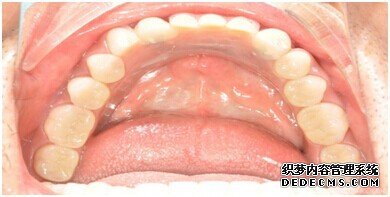

成功植入种植体后的效果图

种植体成功植入后的CT效果图